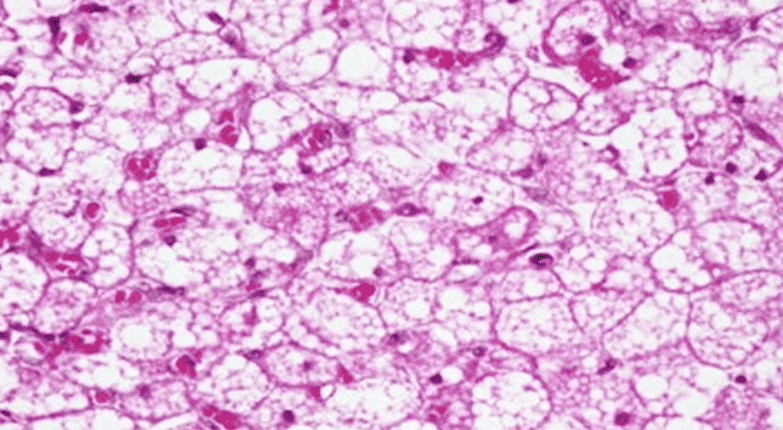

Tecido adiposo multilocular